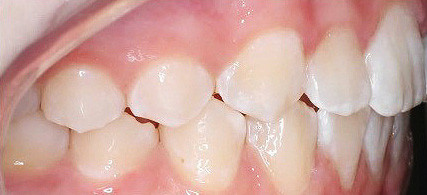

Klinisches Fallbeispiel 2 (Abb. 2a–y)

Distalbiss und tiefer Biss bei einem zwölfjährigen Mädchen. Die Behandlung erfolgte mit Invisalign und Precision Wings. Insgesamt waren zwei Schienensätze notwendig. Die Gesamtbehandlung dauerte 18 Monate.Bei der Planung des ClinCheck wurde der tiefe Biss vorwiegend über eine Intrusion der Unterkieferfront behoben, um die Lachlinie der Patientin nicht negativ zu beeinflussen. Die Oberkieferfront wurde nur retrudiert, jedoch vertikal nicht intrudiert. Während der Phase des Mandibular Advancement wurde die Wirkung der Precision Wings durch den Einsatz von Klasse II-Gummizügen unterstützt. Schlussendlich wurde auch der hängenden Okklusionsebene durch eine einseitige Intrusion der Molaren im ersten Quadranten Rechnung getragen.